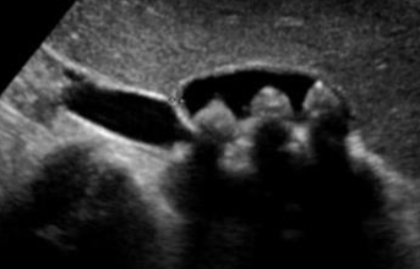

colonscope view of 58 year male complained rectal bleeding

diagnosis

Colonic polyp

Common type lesion ademp,atpis

1- What is your diagnosis?

Sessile colonic polyp.

2- What is the important significant of it ? It has high potential for malignancy.